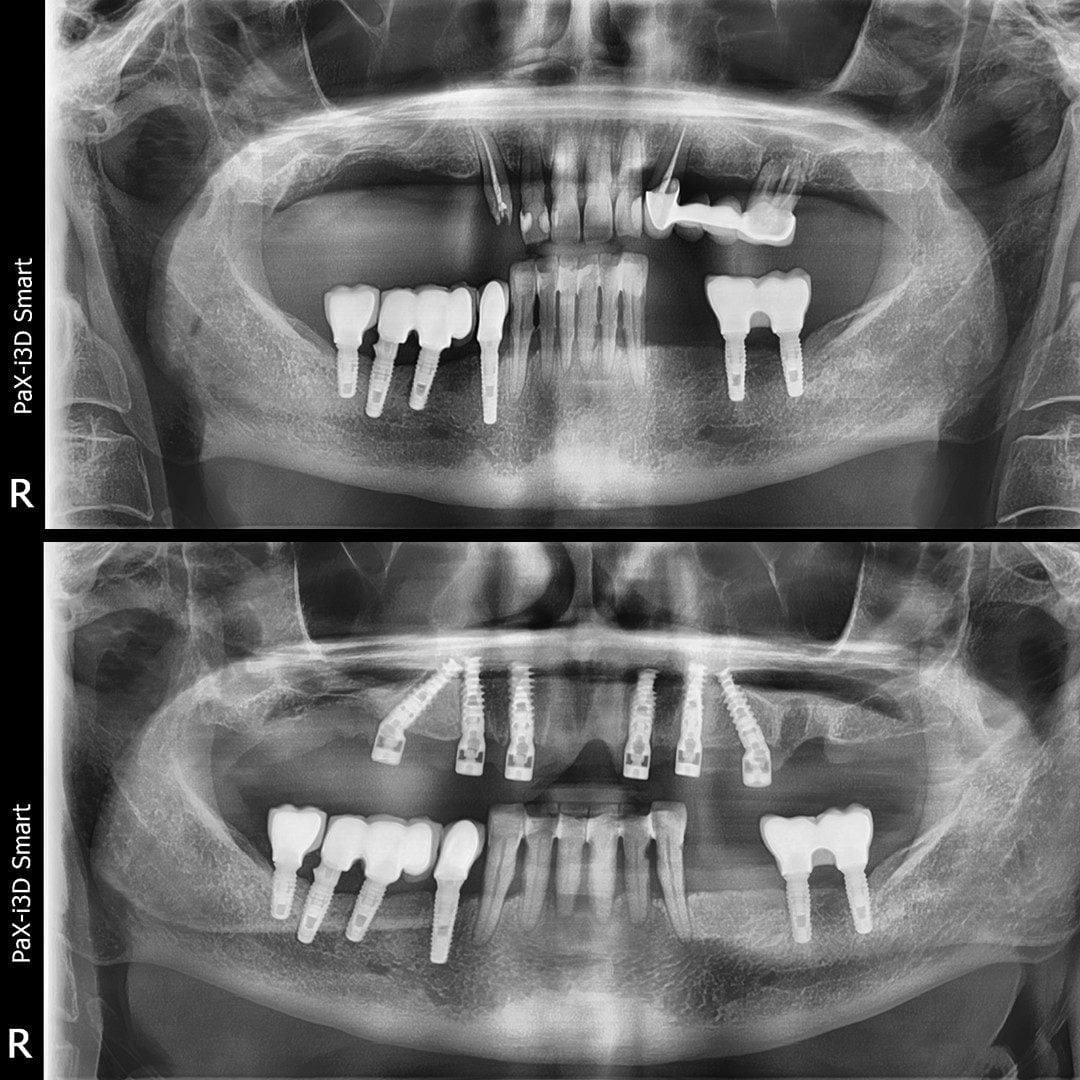

Dinți Ficși în 8-24 de ore pe implanturi dentare cu tehnica All-on-4/All-on-6 este cea mai eficientă și rapidă metodă de restaurare totală a danturii.

- Intervenția chirurgicală

Peste 4000 Implanturi dentare inserate